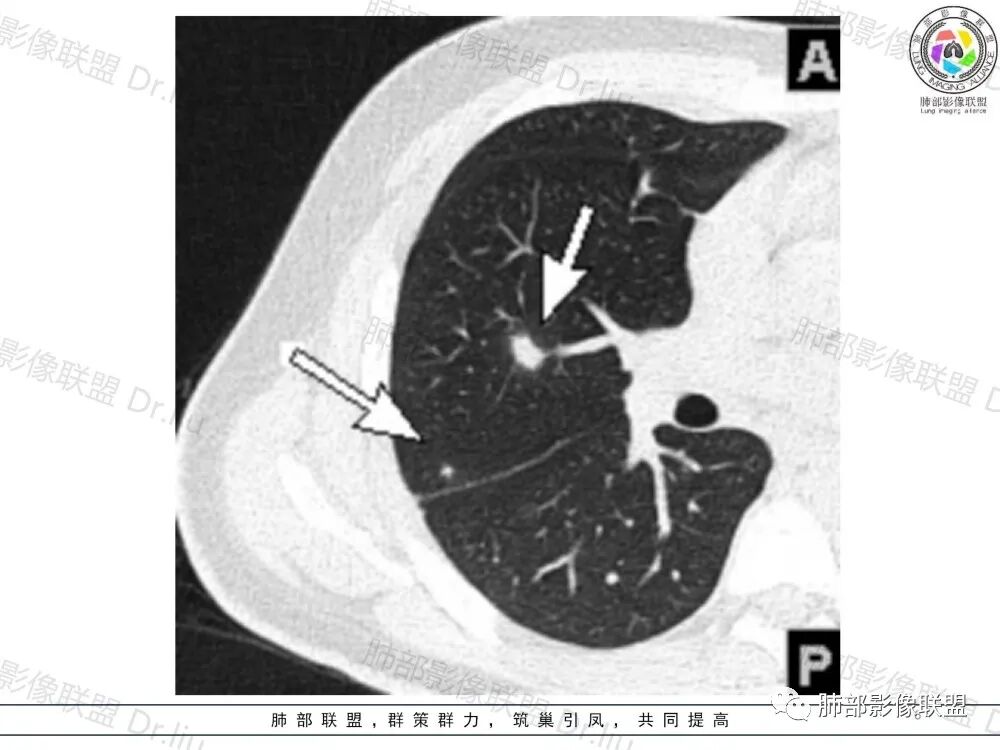

良孑:

双肺多发结节,结节内支气管穿行,前纵隔多发结节样肿大淋巴结,并有融合趋势,血管脂肪间隙模糊,腹部图像不太清楚,似乎有皮革胃,年轻患者,考虑为淋巴瘤

谢加平:

前纵隔多发淋巴结肿大及融合,包绕大血管前缘,双肺叶多发结节,最大者位于中轴间质(淋巴道来源),纵隔和肺同源,淋巴瘤首选!

2、影像特点:两肺可见多发大小不一的结节影,部分结节周围可见晕征,部分结节沿着支气管血管束分布,部分位于胸膜下。前纵隔内可见多发结节样软组织密度影,边界不清,部分病灶融合倾向,其脂肪间隙显示模糊。由于腹腔层面少,未能确定腹腔内有无增大淋巴结,需要连续层面追踪观察。